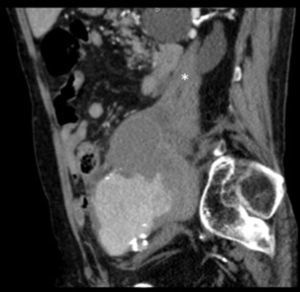

Paciente varón de 86 años, hipertenso en tratamiento con 2 fármacos, con historia de dolor lumbar con irradiación crural derecha de varios meses de evolución que se había controlado parcialmente con tratamiento sintomático. Su reumatólogo le había prescrito RM dorsolumbar que no llegó a realizarse ya que el paciente acudió antes a urgencias por aumento de la intensidad del dolor. En la analítica, hemoglobina 8,4g/dl, LDH 318 U/l, creatinina 1,29mg/dl, PCR 6,16mg/dl, VSG 24mm/h y leve hipoproteinemia. Ausencia de signos de inestabilidad hemodinámica. Se realizó una TC abdominopélvica con contraste por vía intravenosa que muestra aneurismas ilíacos aislados bilaterales>6cm (fig. 1) con rotura contenida del derecho (fig. 2), que desplazaba el músculo psoas (fig. 3) y horadaba el hueso ilíaco ipsolateral (fig. 4). El paciente es sometido a by-pass aortobifemoral pero lamentablemente fallece en el postoperatorio.

Los aneurismas ilíacos aislados, sin aneurisma aórtico asociado, son raros1. Son relativamente difíciles de identificar, ya que hasta un 40% de ellos se pueden presentar con rotura2. La tasa de incidencia de causas extraespinales de ciática es baja3. Igualmente, el aneurisma roto crónico constituye una entidad peculiar. Todas estas circunstancias se aúnan para que el diagnóstico, la mayoría de las veces, sea erróneo y tardío4. Suele tratarse de una rotura laterodorsal hacia las inserciones anteriores del psoas que contiene el hematoma, evitando la extravasación masiva pero no la infiltración de las raíces del plexo lumbosacro, lo que origina un dolor crónico lumbar con irradiación al miembro inferior5, siendo esta su presentación más frecuente6. El diagnóstico puede realizarse con TC abdominal7, pudiendo también visualizarse en la RM lumbar (corte parasagital)7,8. En cualquier momento de la evolución, el aneurisma puede sufrir una rotura aguda secundaria4. Este caso sirve para recordarnos, en nuestra práctica diaria, que la causa aneurismática puede estar implicada en los síntomas de ciática9.